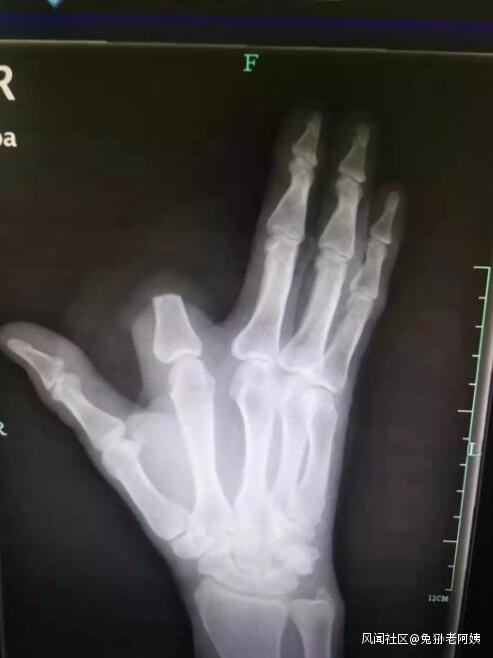

“打開一看,我們發現患者的食指少了一大截。”袁丞達一問,張先生顫抖着回答,“砍了,保命要緊!”

原來,被咬後,張先生仔細一看,發現傷人的是條劇毒五步蛇,怕自己走動後毒性發作,一時恐懼緊張,就拿刀將自己的食指斬斷了。事後,他將斷指就地丟棄,沒有一併帶到醫院。

檢查結果出來,張先生的凝血功能正常,醫生為他注射了抗蛇毒血清。本來,斷指尚可以再植,如今,只能由骨科醫生手術處理斷指殘端,張先生將留下終身殘疾。